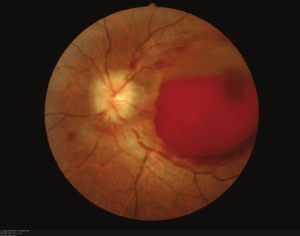

Terson syndrome

Vitreous hemorrhage in association w/ SAH